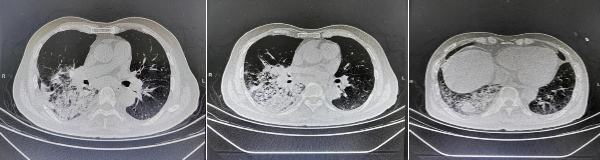

患者王某,因“髮(fa)熱、咳嗽、咳痰1周”于(yu)我(wo)院治療,經(jing)過(guo)影像學(xué)檢(jian)查,初步診斷(duan)“社(she))區(qu)獲得性肺炎(重(zhong)症)、肺占位性病變、高(gao)血壓2級(極高(gao)危)”,經(jing)過(guo)連續10天的(de)抗感染、止咳祛痰、氣(qi)道廓清(qing)等(deng)治療,患者複查肺部(bu)CT:右肺下葉大(da)片滲出,病竈範圍增大(da),右肺下葉不除外郃(he)并占位可(kě)能(néng)。